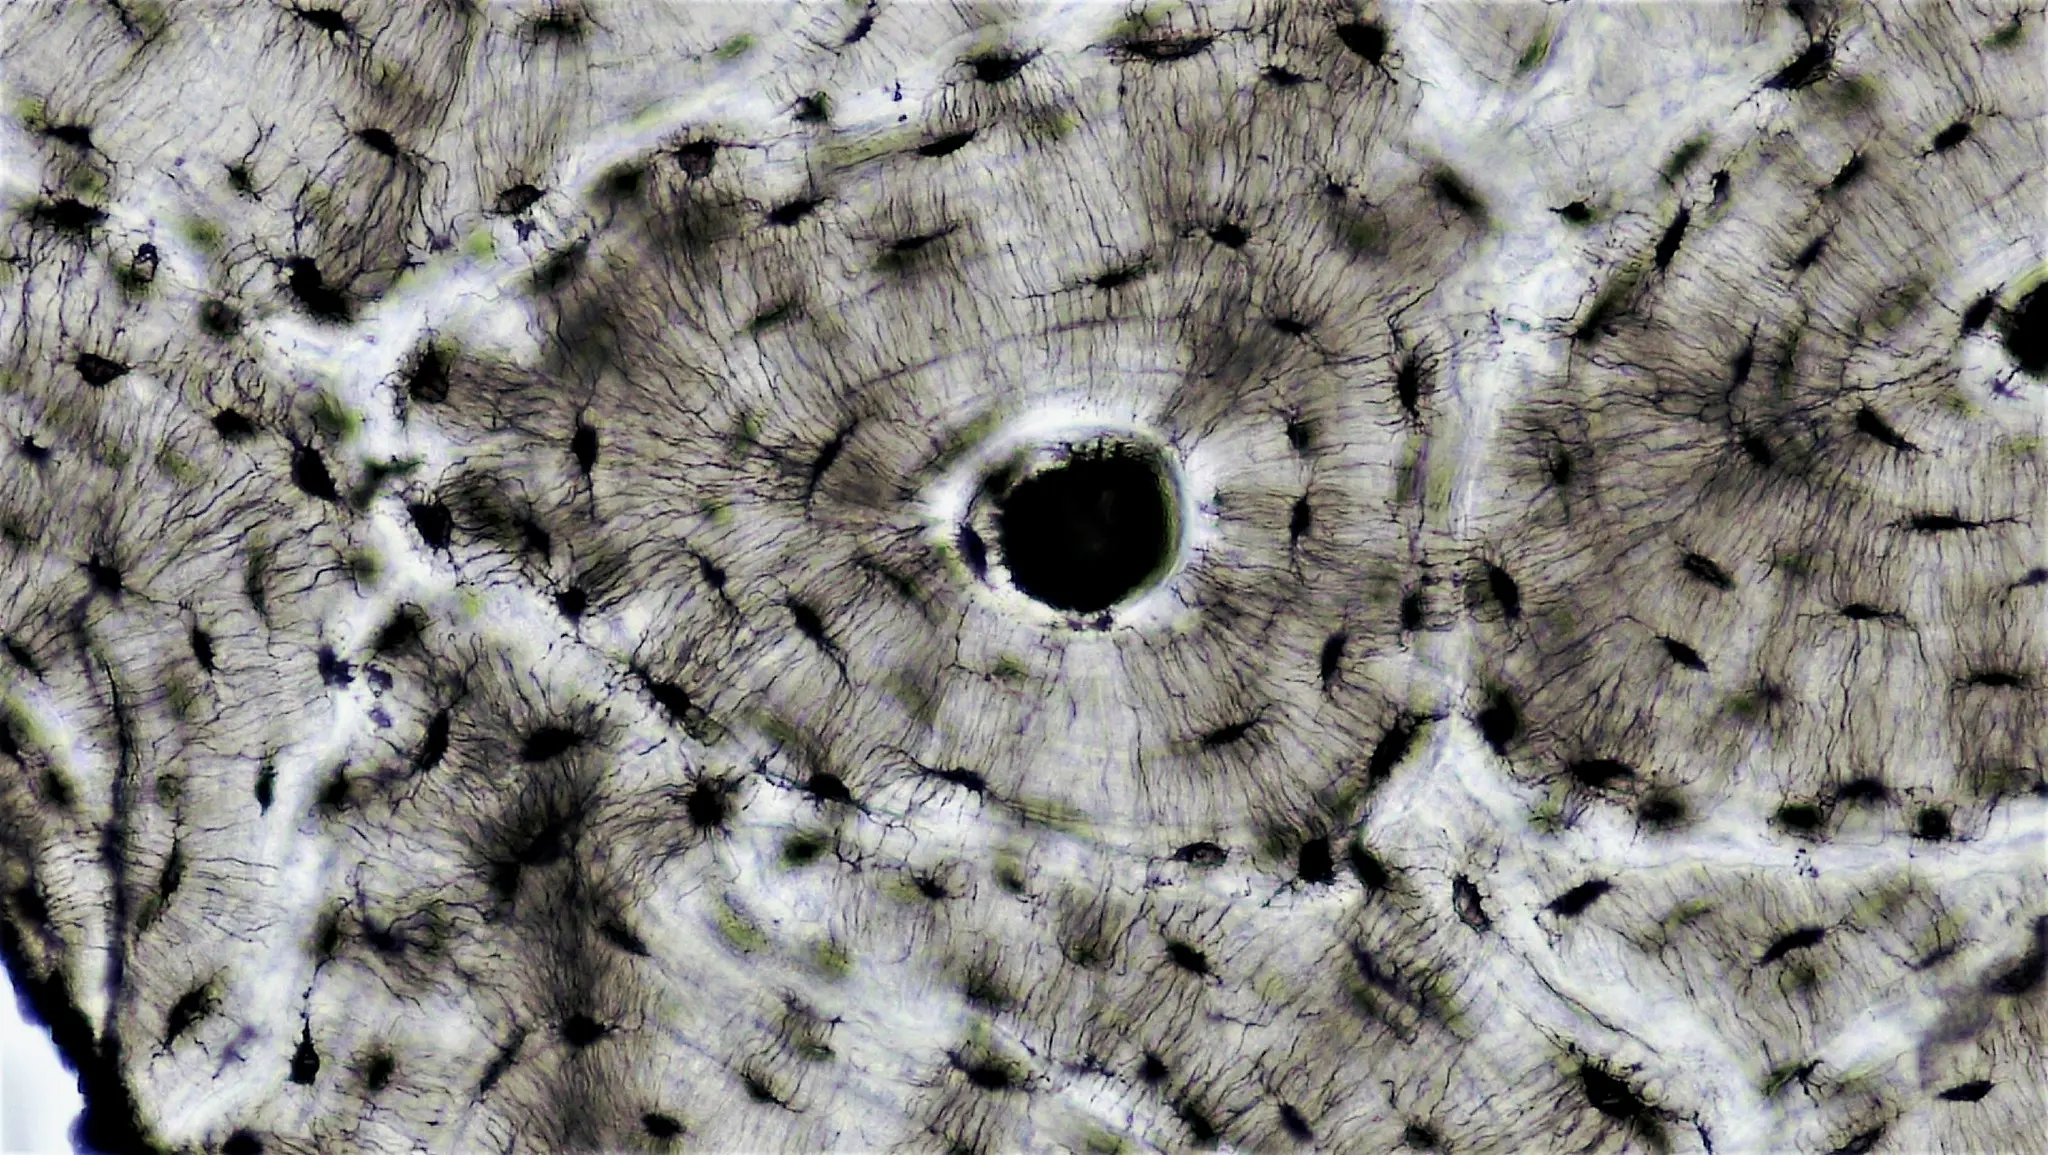

Canale di Havers e canali di Volkmann: anatomia dell'osteone, struttura dell'osso corticale e ruolo nella vascolarizzazione ossea.